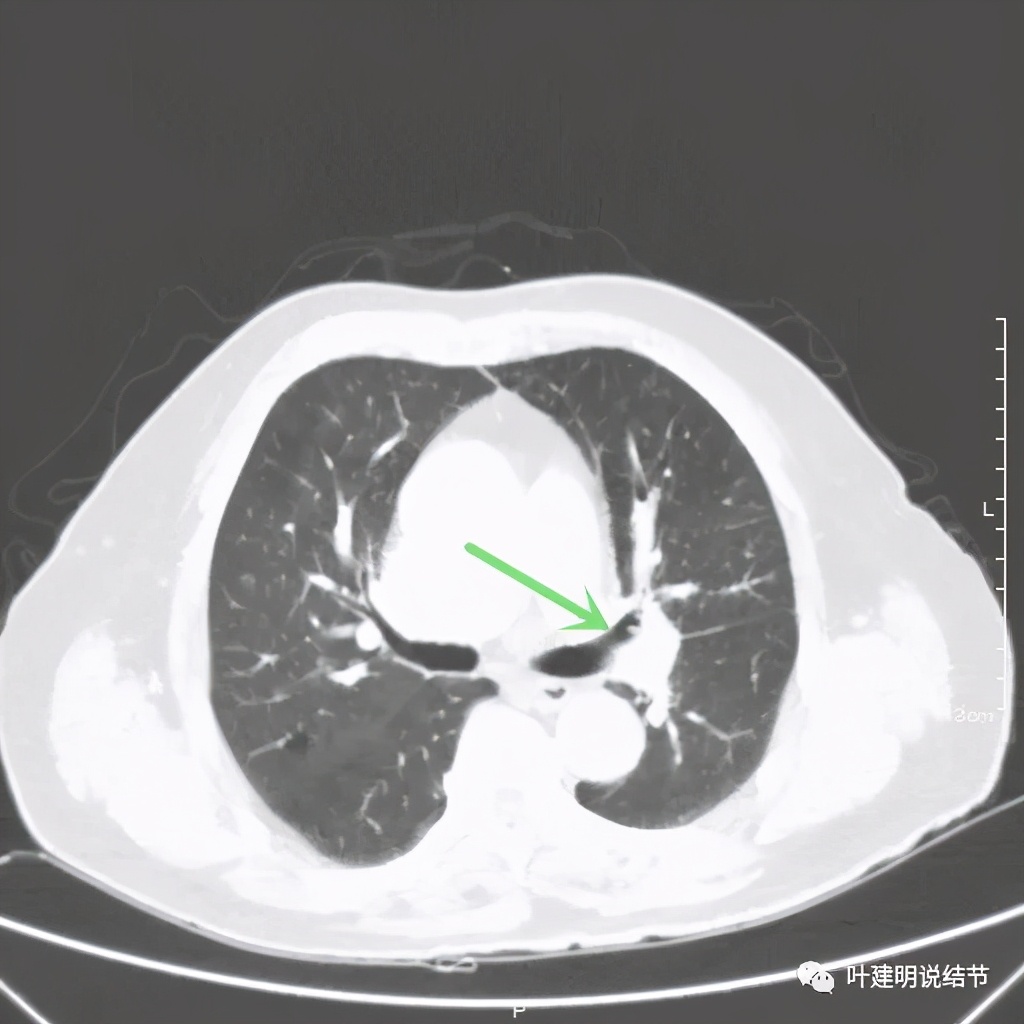

上图绿色示左上叶支气管,蓝色示下叶支气管开口处